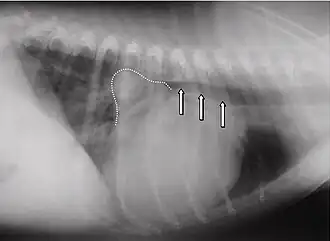

Punctum maximum der Mitralklappe beim Hund im 5. Interkostalraum an der Knorpel-Knochen-Grenze.

Röntgenaufnahme eines Hundes mit Mitralklappeninsuffizienz. Gestrichelte Linie: Mitralisdreieck. Pfeile: vom Herzen nach dorsal verlagerte und kaudal komprimierte Luftröhre.

Die häufigsten Anzeichen einer verschlechterten Herzfähigkeit sind: abnehmende Leistungsfähigkeit, Husten, nächtliche Unruhe und Dyspnoe. In der Auskultation sind in den meisten Fällen holosystolische Herzgeräusche konstanter Intensität in verschiedensten Lautstärken (Grad 1 bis Grad 6) wahrnehmbar. Das lauteste Geräusch (Punctum maximum) der Mitralklappe liegt beim Hund im 5. Interkostalraum auf Höhe der Herzspitze. Im Röntgenbild ist häufig ein vergrößertes Herz feststellbar. Der linke Vorhof kann hierbei in Form eines Dreieckes („Mitralisdreieck“) nach kaudo-dorsal hervortreten. Die häufig feststellbare Abwinkelung zwischen Luftröhre und Wirbelsäule kann einem parallelen Verlauf gewichen sein, teilweise kann der Vorhof sogar die Luftröhre komprimieren und infolge der hierdurch verursachten mechanischen Reizung die Hustensymptome noch verstärken. In fortgeschrittenen Fällen liegt ein Lungenödem vor. Das Elektrokardiogramm ist häufig wenig spezifisch, teils sind Hinweise auf einen vergrößerten Vorhof (verlängerte P-Welle, über 0,04 Sekunden) oder eine vergrößerte Hauptkammer (QRS-Komplex länger als 0,06 Sekunden) erkennbar. Daneben kann es zur Ausbildung von Vorhof- oder Kammerextrasystolen kommen, in einigen Fällen wird ein Vorhofflimmern beobachtet. Dieses Symptom ist bei Hunden mit funktionellen Mitralinsuffizienzen aufgrund einer dilatativen Kardiomyopathie häufig. Echokardiografisch ist eine Mitralklappeninsuffizienz anhand einer Doppleruntersuchung leicht erkennbar. Daneben treten als Effekte auf: erweiterte Hauptkammer aufgrund der Volumenüberlastung, häufig Hyperkontraktilität aufgrund von Kompensationsmechanismen, deutlich vergrößerter Vorhof.